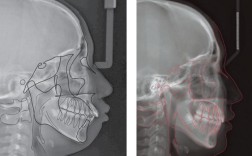

正畸头颅侧位片摆放如何规范?关键步骤有哪些?

📍一、核心目标标准化定位:确保每次拍摄(同一患者不同时间点)和不同患者之间的影像具有高度的可比性,准确测量:提供精确的解剖结构位置信息,用于测量骨骼、牙齿、软组织的角度、距离、比例等,反映自然姿势:尽可能反映患者头颅在自然状态下的...